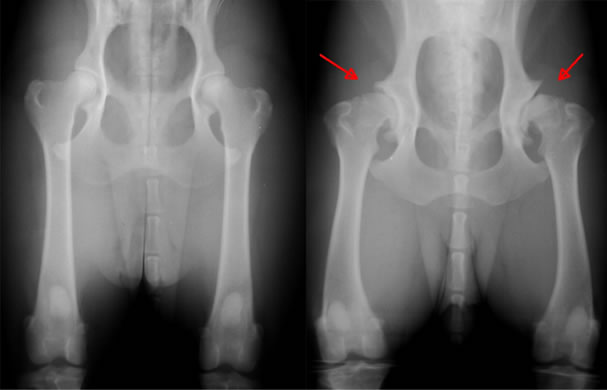

For example, they often have dysplasia of the hip joints, diabetes, and hypothyroidism. Among other common ailments characteristic of dogs of this breed, such problems as aortic stenosis, melanoma and cataract can be noted.

hip dysplasia